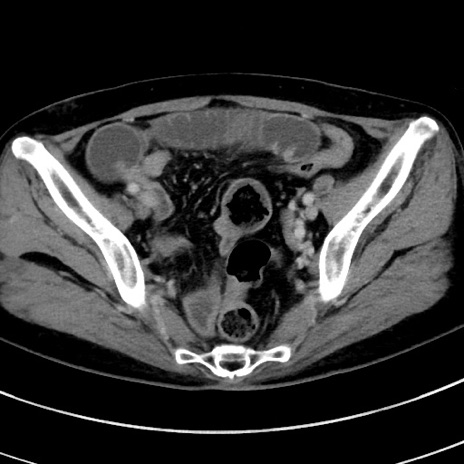

冠状断像